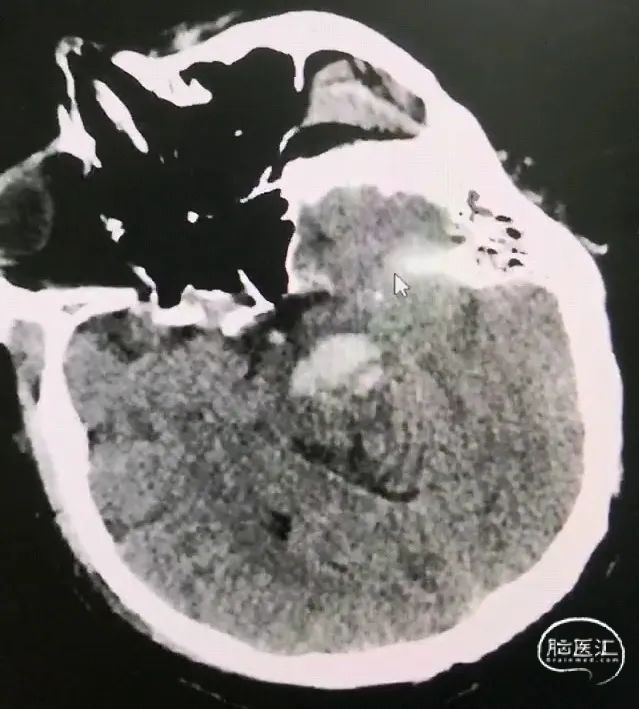

对波及大脑脚、中脑、桥脑上部的上下狭长型血肿,采用经额入路,避开侧脑室,经额叶-内囊前内侧-大脑脚入路,最好沿血肿长轴,靶点选择位置较低、血肿较大的层面;

CT扫描后测算脑干血肿穿刺靶点及路径

脑室及血肿腔平行双管

脑干血肿引流管经大脑脚入中脑

引流管穿经中脑血肿

引流管准确到达靶点

术后尿激酶应用,术后3天复查CT,血肿引流满意